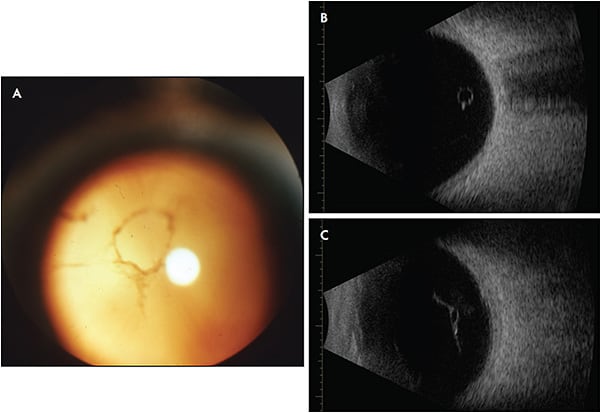

One randomized prospective study used YAG laser to treat visible Weiss rings (Figure 1) in 52 subjects, comparing results to sham treatment.1 The study design was flawed, however, because it was not truly masked, the sham techniques were not properly validated, and there were biases.4 While the YAG laser group reported more frequent symptomatic improvement (54%) than controls (9%; P<.001), this only occurred in about half of the subjects.5 Furthermore, although VFQ-25 had statistical improvements, the findings had little clinical significance, because the magnitude for dependency, role difficulties, near vision, color vision, peripheral vision, and distance vision ranged from only 2.8% to 11.5%. In fact, general vision actually worsened by 3.5%.5